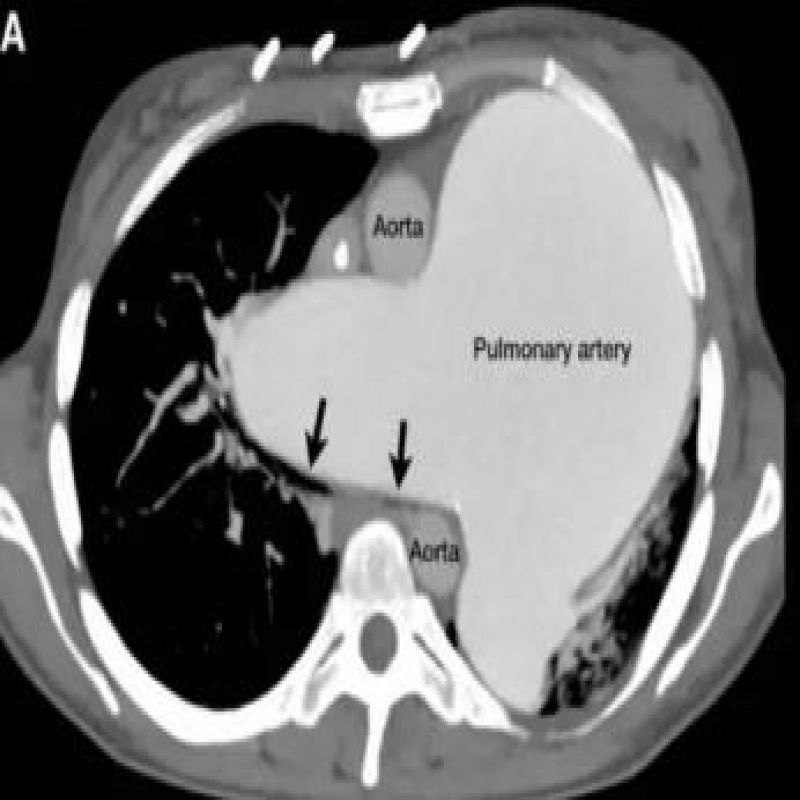

麻醉病例︱一例肺动脉严重扩张患者的麻醉管理